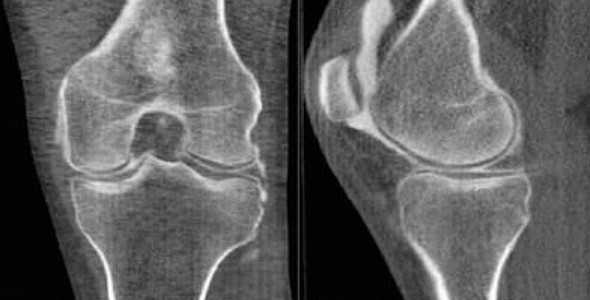

КТ при нестабильности плеча

А - дисплазия гленоида;

В - повреждение Хилл-Сакса (субхондральный перелом), дефект головки плечевой кости после вывиха плеча;

С - повреждение Банкарта (отрыв ободка от костной впадины с вывихом плеча вперед, разрушение краев лопаточной впадины - места прикрепления хряща);

D - повреждение Хилл - Сакса в переднем отделе суставной губы;

Е - 3D-реконструкция переднего вывиха плеча;

F- задний перелом с вывихом плеча.

Наиболее часто КТ плечевого сустава выполняют по поводу травматических повреждений. Они различаются по механизму альтерации: падение на вытянутую руку, прямой удар и пр. Врач-рентгенолог после анализа томограмм выявляет причину, а ортопед определяет оптимальную тактику ведения. Иногда повреждение может быть настолько серьезным, что пациенту необходимо эндопротезирование плечевого сустава.

Рентгенограмма и компьютерная томограмма у пациента с тяжелым переломом и вывихом правого плечевого сустава до операции

При соблюдении всех рекомендаций (ношение ортеза, дальнейшая разработка, динамическое наблюдение с контрольной КТ плеча и пр.) качество жизни не страдает.

На КТ хорошо видны костные дефекты и дефекты гиалинового хряща суставной впадины. Гиалиновый хрящ, покрывающий головку плечевой кости виден гораздо хуже.

КТ плечевого сустава, Переломы Банкарта и Хилла-Сакса.